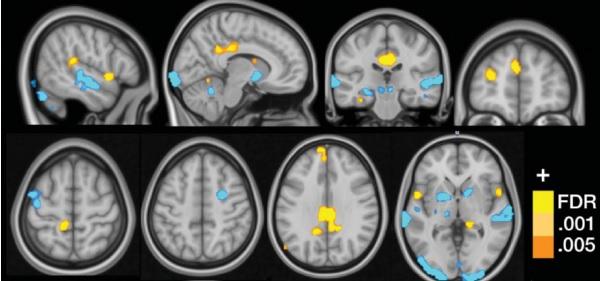

La fibromyalgie est généralement définie comme une douleur musculo-squelettique chronique généralisée accompagnée de symptômes tels que la fatigue, l'anxiété et des troubles de l'humeur. Historiquement, la maladie a été difficile à diagnostiquer -donc à reconnaître-, et à traiter, en raison de symptômes communs avec d'autres maladies chroniques courantes. Mais alors que progressent la reconnaissance et la sensibilisation à la fibromyalgie, une maladie qui touche de 2 à 6% de la population, de nombreuses équipes commencent à travailler à des tests de diagnostic, génétiques, ophtalmiques ou par imagerie. Il s'agit d'aider les cliniciens à mieux diagnostiquer et traiter la fibromyalgie, de manière plus personnalisée. Ici, les chercheurs de l'Université du Colorado identifient une signature du cerveau qui caractérise, avec une précision de 93%, les patients souffrant de fibromyalgie. Il s'agit d'une image IRM qui prédit la fibromyalgie sur la base de l'activation du cerveau pendant une stimulation multisensorielle (Voir visuel ci-contre). Les chercheurs ont utilisé précisément l'IRM fonctionnelle (IRMf) pour étudier l'activité cérébrale de 37 patients atteints de fibromyalgie vs 35 patients témoins en bonne santé, tout en exposant ces participants à toute une variété de signaux visuels, auditifs et tactiles (non-douloureux et douloureux). On sait que l'hypersensibilité sensorielle est caractéristique de la maladie. Ces expériences « multisensorielles » ont permis aux chercheurs d'identifier une série de 3 marqueurs ou « motifs neurologiques » en corrélation avec l'hypersensibilité à la douleur qui caractérise donc la fibromyalgie. Une signature en forme de « motifs neurologiques » : ces travaux apportent ainsi un nouvel outil de neuroimagerie capable d'évaluer le degré de symptômes de douleur, associée -plus largement- à toute une série de neuropathies, explique Marina López-Solà, chercheur en santé cognitive et auteur principal de l'étude : « Un outil d'imagerie précieux pour identifier aussi les sous-types de patients, ce qui peut permettre de mieux personnaliser les traitements ». Reconnaître la fibromyalgie pour ce qu'elle est : Si aujourd'hui, quelques spécialistes de la douleur ont établi des procédures cliniques pour le diagnostic de la fibromyalgie, la description clinique n'explique pas ce qui se passe au plan neurologique et ne reflète pas l'individualité de la souffrance des patients. De telles mesures cérébrales peuvent éclairer les cliniciens sur des anomalies cérébrales particulières qui conduisent à la souffrance d'un patient. Enfin, un tel outil, contribue aussi à faire « reconnaître la fibromyalgie pour ce qu'elle est, un trouble du système nerveux central ».

August 31, 2016 doi: 10.1097/j.pain.0000000000000707 Towards a neurophysiological signature for fibromyalgia. (Visuel@Cognitive and Affective Control Laboratory / University of Colorado Boulder)